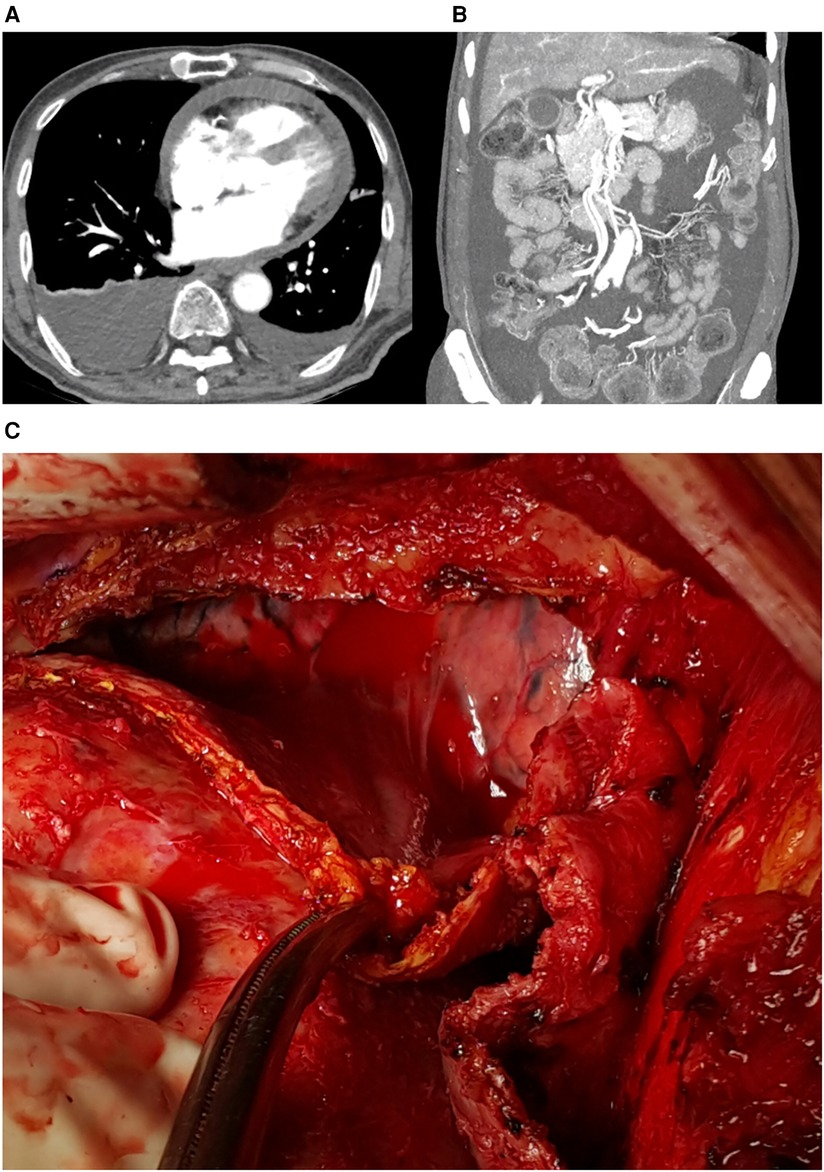

The patient visited the emergency room two weeks after discharge due to worsening abdominal distension and dyspnea. At presentation, his blood pressure was 95/60 mmHg and heart rate was 70 beats/min. His physical exam was remarkable for grade 2 pitting edema at the lower extremities, a marked jugular venous pulse, pericardial friction rub on ascultation, and a distended abdomen with shifting dullness. Laboratory findings included mildly elevated liver enzymes, with aspartate aminotransferase at 56 U/L and alanine aminotransferase at 64 U/L, and total bilirubin 1.3 mg/dl. A follow-up echocardiogram revealed pericardial thickening and adhesion at the apex and RV anterior wall, along with scanty pericardial effusion. Intraventricular septal bouncing and respiratory mitral and tricuspid valve inflow variability suggested constrictive pericarditis (Figure 2, Supplementary Video S1). Additionally, global hypokinesia resulted in a decreased LVEF of 39%. Large amounts of pleural effusion and ascites were apparent on CT scans of the chest and abdomen, the latter of which was identified as transudate by paracentesis (Figures 3A,B). Unfortunately, due to the patient's instability, right heart catheterization could not be performed.

Figure 3. (A) Pericardial effusion, pleural effusion, and (B) ascites on computed tomograph, (C) intraoperative findings: thickened pericardium and hemopericardium.

The patient underwent surgery due to increasing oxygen requirements and hemodynamic instability. Intraoperative findings revealed a thickened (5 mm) and slightly adhesive pericardium without calcifications, and a dark bloody effusion was drained after opening of the pericardium (Figure 3C). Radical pericardiectomy was performed on the anterior, diaphragmatic, and posterior pericardium under cardiopulmonary bypass, and the operation was concluded without major complications. Pathology was negative for tuberculosis, and was unremarkable except for thick fibrosis without evidence of active inflammation. After the operation, the patient experienced significant relief from symptoms such as abdominal distension and dyspnea. Postoperative care was uneventful, and the patient was discharged on diuretics. Minimal remaining septal bouncing was noted on a follow-up echocardiogram two months after surgery, but no other indicators of constrictive physiology were observed. The patient occasionally complains of intermittent chest pain, but is otherwise stable at outpatient follow-up, two years after the surgery. The patient's timeline is presented in Table 1.